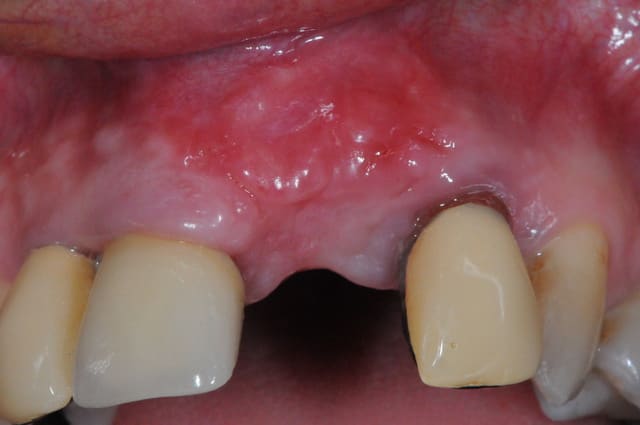

Voila un exemple de conjonctif pédiculé palatin.

Les gros avantages par rapport à ta technique sinclair sont :

1- mobilisation d'un plus gros volume de tissus pour gonfler en vestibulaire.

2- cicatrisation de première intention au niveau du palais puisque l'ensemble du site prélevé est couvert par ta fenêtre d'accès

3- peu de suite post opératoire.